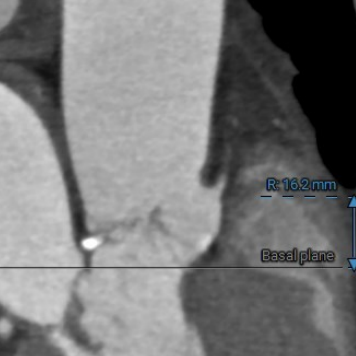

右冠开口高度:

16.2mm

● 主动脉根部:患者主动脉瓣为三叶瓣,左右冠窦可见部分粘连,重度钙化,瓣环到LVOT层面可见钙化,法式窦结构较大,左冠开口高度约11.0mm,右冠开口高度约16.2mm,STJ高度约19.5mm,直径约28.1mm,升主动脉未见明显扩张,心脏角度约49°,左室形态稍小,心肌增厚。